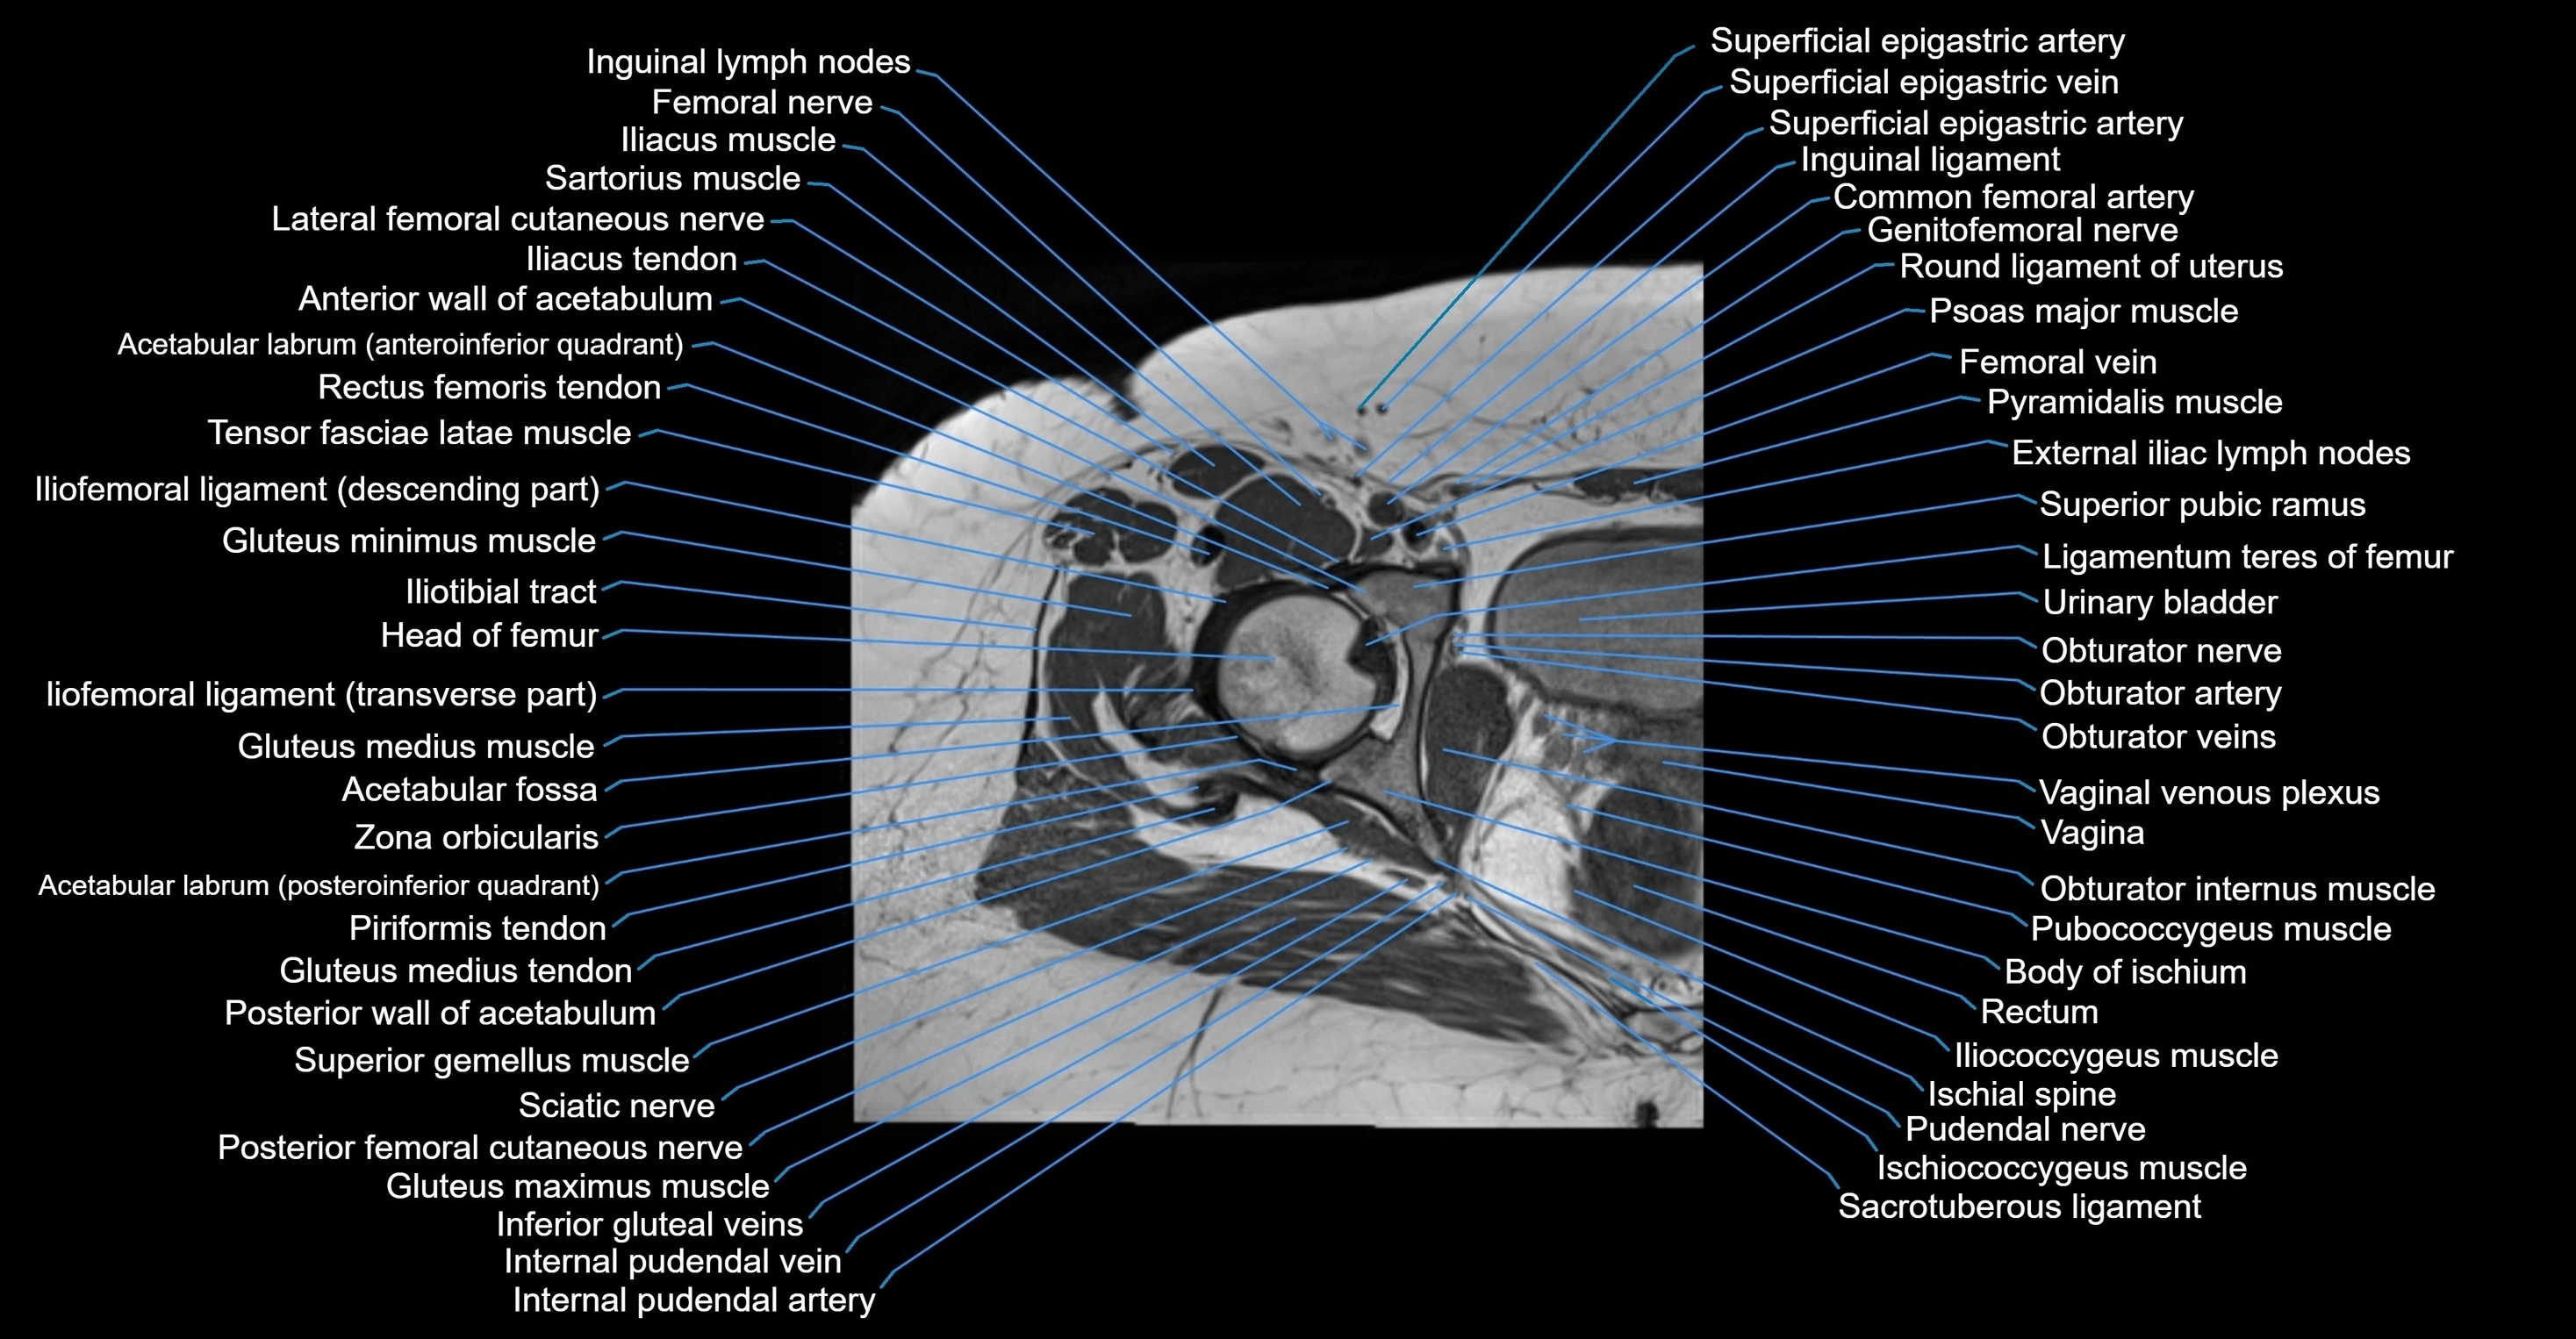

- External iliac lymph nodes

- Femoral nerve

- Femoral vein

- Genitofemoral nerve

- Gluteus maximus muscle

- Gluteus medius muscle

- Gluteus medius tendon

- Gluteus minimus muscle

- Iliococcygeus muscle

- Iliopsoas tendon

- Iliotibial tract

- Inguinal ligament

- Inguinal lymph nodes

- Ischial spine

- Ischial tuberosity

- Ischiococcygeus muscle

- Lateral femoral cutaneous nerve

- Ligamentum teres (ligament of the head of femur)

- Obturator externus muscle

- Obturator internus muscle

- Obturator internus tendon

- Obturator nerve

- Obturator vein

- Obturator veins

- Pubococcygeus muscle

- Pudendal nerve

- Pyramidal muscle (pyramidalis muscle)

- Rectus femoris muscle

- Rectus femoris tendon (Proximal tendon of rectus femoris)

- Round ligament of uterus

- Sacrotuberous ligament

- Sartorius muscle

- Tensor fasciae latae muscle

- Urinary bladder

- Vagina

- Vaginal venous plexus

- Vastus lateralis muscle

- Zona orbicularis ligament